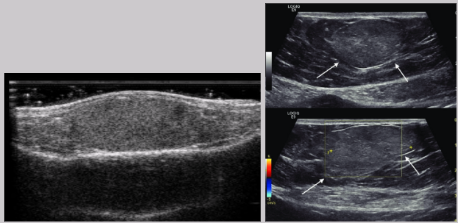

Seroma

Collection of serum in the tissue

Results from a surgical incision or liquefaction of a hematoma

Distinct from hematomas because they contain no red blood cells

US Findings:

Anechoic cystic structure

Well-circumscribed

Posterior enhancement